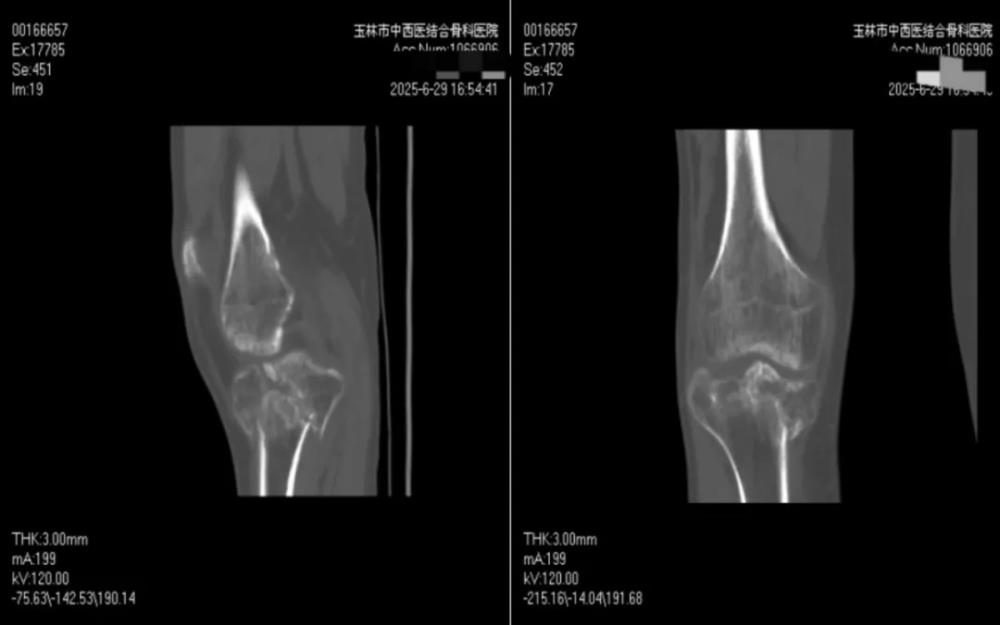

转机出现在亲友的推荐下。罗某抱着一丝希望,跨越三小时路程,从柳州来到玉林市中西医结合骨科医院,慕名求诊于膝关节病与运动损伤科朱博副主任医师。经朱博医师细致检查,确诊为“右胫骨平台陈旧性粉碎性骨折”,骨折端粉碎严重,移位明显,关节面塌陷,且已畸形愈合,手术难度极大。

面对挑战,膝关节病与运动损伤科科主任黄丽雄所带领的膝关节运动与损伤科团队并未退缩,手术团队充分利用医院的3D临床打印中心”。这一创新平台,为罗某实施了个性化术前规划:将膝关节CT扫描数据导入软件,启动建立膝关节模板,使用MultipleSliceEdit模组编辑像素合集,对骨折块进行提取、分割及着色并转换为三维模型。在3D 对象窗口下,观察骨折的塌陷情况、移位距离及旋转角度,使用移动和旋转功能对各个骨块进行移动复位,将虚拟复位前、后的三维模型保存,经3D打印机等比例精准3D打印复制出患者受损的胫骨平台模型。这一技术犹如赋予医生一双“透视眼”,骨折线的走向、碎骨块的位移形态、关节面塌陷的程度等复杂情况在模型上清晰直观、一目了然。

朱博副主任感言:罗先生的病例极具挑战性,胫骨平台粉碎性骨折,属Schatzker Ⅴ型,过伸内翻型胫骨平台双髁骨折,即使新鲜骨折手术难度就较大,加之外伤后3个多月,骨折已畸形愈合,手术难上加难。是三维CT及3D打印技术带来的‘术前透视’能力与团队多年积累的临床经验相结合,才创造了这次成功。我们将持续探索创新技术应用,以更精准、更微创、更高效的方式,守护每一位骨伤患者重新站立的权利。